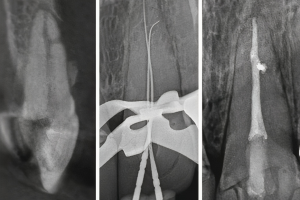

Радиационно-индуцированный некроз или остеорадионекроз характеризуется наличием обнаженной кости после проведения лучевой терапии. Открытая кость может полностью секвестрировать, что часто приводит к обнажению большего количества кости. Хотя кость, расположенная в любом месте челюсти, восприимчива к излучению, задняя часть нижней челюсти поражается чаще, чем другие области, потому что она часто находится в поле излучения, особенно когда в лечение включены лимфатические узлы. Может возникать интенсивная боль при периодическом отеке и дренировании вне полости рта. Однако многие пациенты не чувствуют боли при обнажении костей. Утрата нормальной структуры может нарушить целостность кости, а в некоторых случаях кость может сломаться.